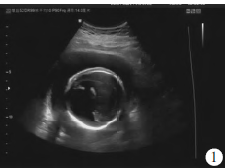

孕妇39岁,妊娠5月余,既往无感染史及放射接触史,无畸形分娩家族史。超声表现:宫内见一个胎儿,可见胎头光环,双顶径6.2 cm,头围21.1 cm,腹围18.5 cm,股骨径4.7 cm,肱骨径4.2 cm,胎盘后壁,厚2.5 cm,羊水指数26 cm,胎心155次/min。胎儿颅内仅见原始脑室,中央可见融合的丘脑,脑中线、透明隔腔及第三脑室消失(图1)全前脑畸形。

图1胎儿全前脑颅内超声表现